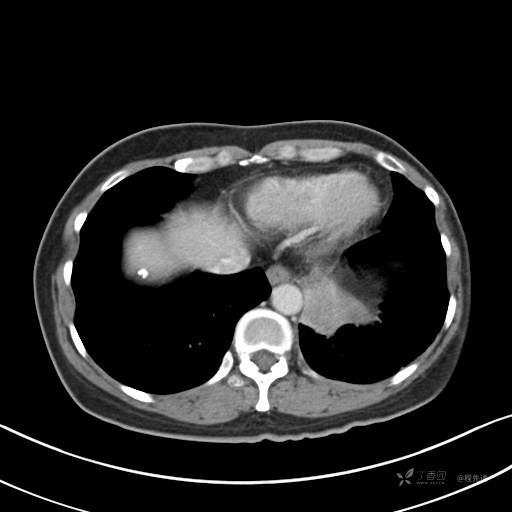

冠状位重建

CT值:平扫:31HU,动脉期:74HU,静脉期:84HU